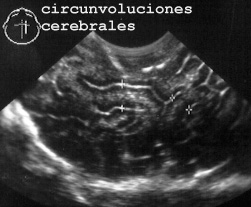

ventrículos laterales y el tercer ventrículo, valoración de su tamaño y el de la corteza (Fig 62)

62CIRCUN.JPG (21208 bytes)

Fig 62